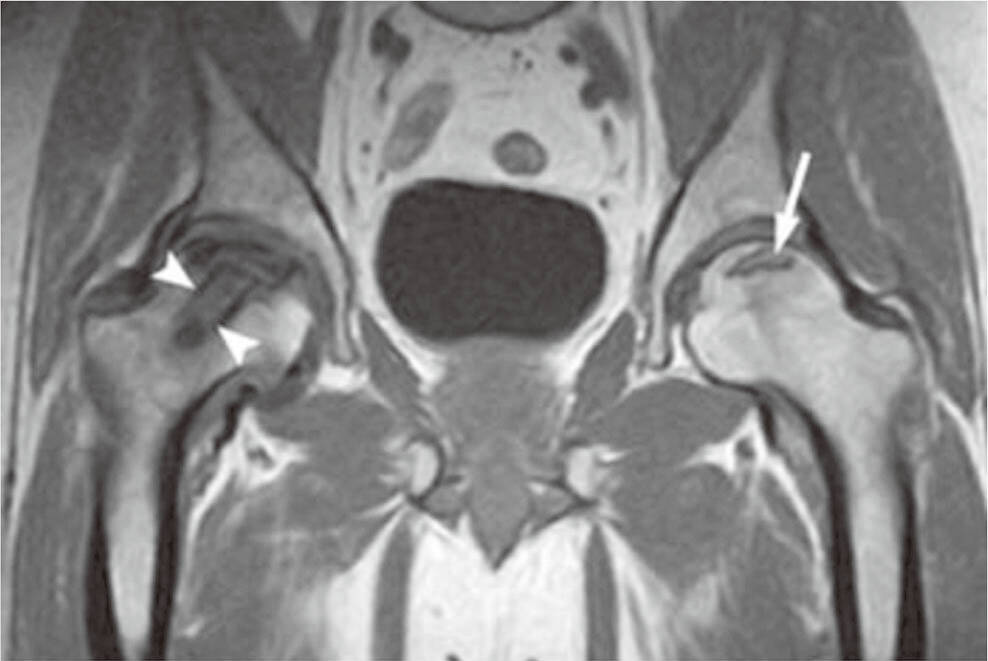

对于怀疑有 股骨头坏死的人群,应尽快寻求专业机构的评估,尤其是在 衡水股骨头医院等专业医疗机构进行全面检查。医生可能会通过影像学检查来确认病情。在确诊后,采用 股骨头坏死保守治疗方法如药物治疗、物理治疗等,可以帮助缓解症状并阻止病情进一步恶化。了解这些早期信号,有助于患者更好地应对自身健康问题。

股骨头坏死的成因多种多样,常见的有长期使用类固醇药物、酗酒、外伤及血液供应不足等。这些因素可能导致骨细胞缺氧、死亡,进而引发坏死。早期发现症状,如髋关节疼痛和活动受限,有助于及时进行疾病干预。关于股骨头坏死保守治疗,现有研究显示,通过物理治疗和药物管理等方法,可缓解疼痛,改善关节功能。尽管部分患者可能恢复良好,但也需考虑到个体差异、病程发展等因素。因此,无论病症的严重程度如何,选择专业机构如衡水股骨头医院进行系统评估和个性化治疗方案,都是极为重要的。